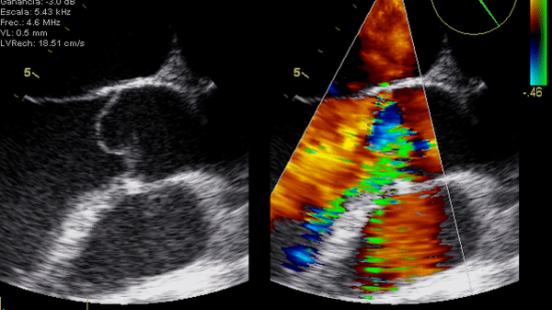

Gracias al uso de ultrasonidos, la ecocardiografia permite estudiar el tamaño, el funcionamiento y los movimientos del corazón. Esta es la técnica diagnóstica más utilizada en cardiología. A pesar de que los cardiólogos son los profesionales sanitarios que mejor dominan este procedimiento, hay otros profesionales que también necesitan conocer cómo funciona. Como explica el Dr. Artur Evangelista, director del Curso Teórico-práctico de Ecocardiografía Básica y de Ecocardiografia Avanzada en Medicina Intensiva, Anestesia y Reanimación, “médicos de familia, internistas o neurólogos también necesitan realizar ecocardiografías para tratar a sus pacientes”. De este modo, el Curso Teórico-práctico de Ecocardiografía Básica y de Ecocardiografía Avanzada en Medicina Intensiva, Anestesia y Reanimación consta de dos partes. “Una primera parte de conocimientos básicos para que estos profesionales, y también los cardiólogos que están empezando, puedan realizar ecocardiografías y detectar posibles problemas. La ecocardiografía te da imágenes de cómo está el corazón, pero estas imágenes, está claro, se tienen que saber interpretar, que es lo que enseñamos en este curso —señala el Dr. Artur Evangelista—. Si estos profesionales detectan alguna posible patología, después pueden derivar al paciente al cardiólogo, que es el especialista”.

El curso ha combinado seminarios teóricos y talleres prácticos para mostrar, entre otros aspectos, las bases de la ecocardiografía y la anatomía ecocardiográfica, la optimización del ecocardiógrafo, el Doppler cardíaco, el uso de la ecocardiografía en el shock, el dolor torácico agudo, el síndrome coronario agudo, la insuficiencia cardíaca, el preoperatorio, la ecocardiografía transesofàgica o la ecografía pulmonar. Uno de los aspectos más destacados ha sido el uso de simuladores, para acercar la formación a las situaciones reales de práctica clínica que se pueden encontrar los profesionales. Los simuladores aumentan la destreza en el estudio y la interpretación de las imágenes y permiten analizar un amplio número de patologías. Esta herramienta se ha convertido en un elemento imprescindible en la formación teórico-práctica en ecocardiografía.